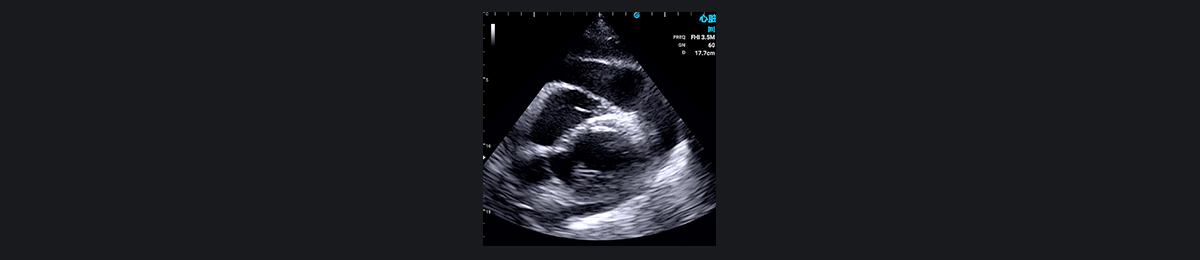

心包积液